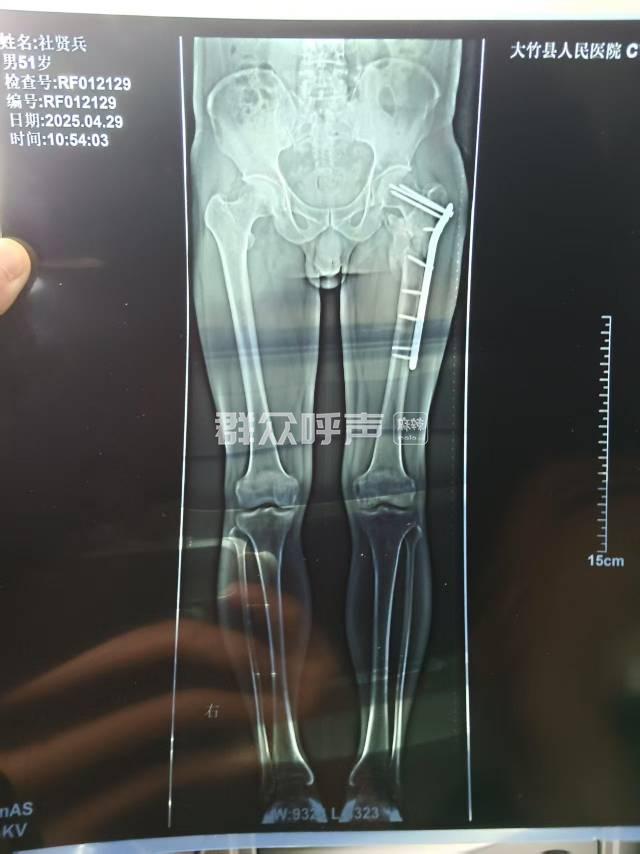

[投诉] 四川省卫生健康委员会投诉信